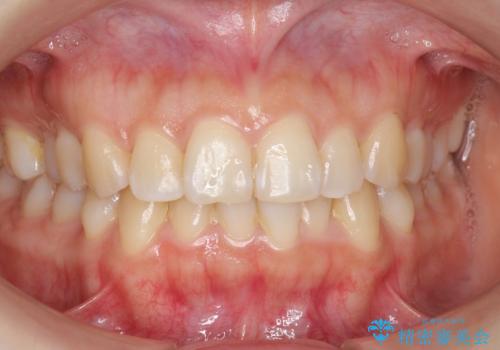

下の前歯のがたつき インビザラインで

- 前歯のがたつきを主訴に来院。

インビザラインで上下の前歯をわずかに削って並べました。

下の歯の叢生を並べると多少ブラックトライアングルがでることがあります。